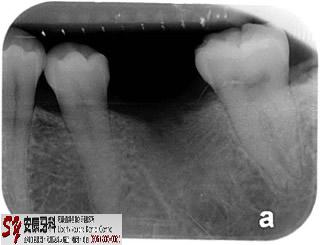

Lower Left First Molar:

First molar is the first adult tooth erupting into the mouth.

It is very commonly the first tooth to lose due to cavity/decay.

A root-form dental implant was placed in the jaw bone to replace the root of the missing molar.